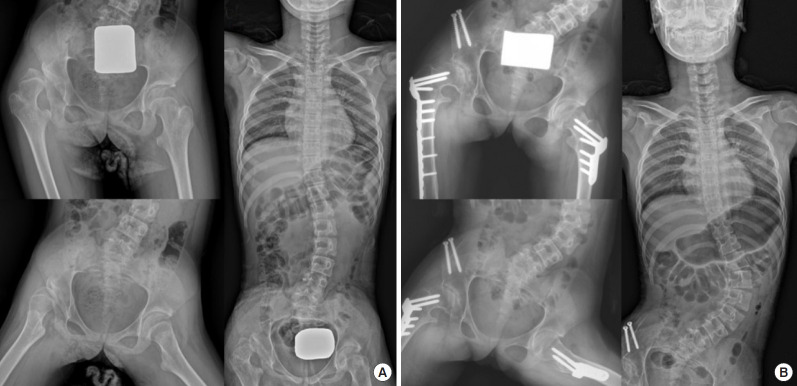

Hip dislocation and scoliosis are common in children with CP or other neuromuscular diseases. There was a concern that the pelvis can become a stiff “end vertebra” that prevents compensatory mechanisms from adjusting to hip deformities. Crawford et al. [6] reported that 45% (21 of 47) of neuromuscular patients who underwent posterior spinal fusion required a hip procedure, either before or after spinal surgery with an average follow-up of 3.5 years. In patients who had containment surgery of the hip before posterior spinal fusion, the hips maintained the reduction after spinal fixation, and new hip subluxation/ dislocations occurred in 8 cases (17%) after correction of pelvic obliquity. However, the development of subluxation and dislocation of the hip is multifactorial. Current expert opinion suggests that when hip dislocation and scoliosis are present at the same time, scoliosis-associated pelvic obliquity should be corrected before hip reconstruction; however, whether adequate treatment of the hip prevents scoliosis or vice versa in patients with CP remains unclear [7]. The close observation of the progression of hip dislocation or scoliosis after surgical treatment of one of these problems is important in patients with neuromuscular disease (Fig. 1).

Fig. 1.

(A) An 11-year-old girl with spastic quadriplegic cerebral palsy had a right hip dislocation and 37° of scoliosis from T11 to L4 in supine radiography. (B) At the postoperative 2-year follow-up after reconstructive surgery for hip dislocation, the reduction of the hip was maintained, but the scoliosis had progressed to 82° from T11 to L4 in supine radiography.